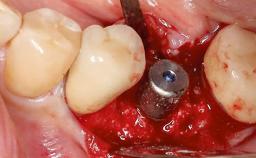

Surgical Management of Peri-Implantitis: Removal of Implant Due to Recurrent Infection Using an Implant-Retrieval Tool

Despite anti-infective surgical treatment, some patients may experience recurrent infection and progressive bone loss requiring additional treatment. This case describes a conservative approach using an implant retrieval tool without the need for excessive bone removal or use of a trephine.

A 65-year-old female patient was referred to the periodontist for assessment and management of infection associated with an implant at site 12. The general dentist had noted suppuration on probing during examination.